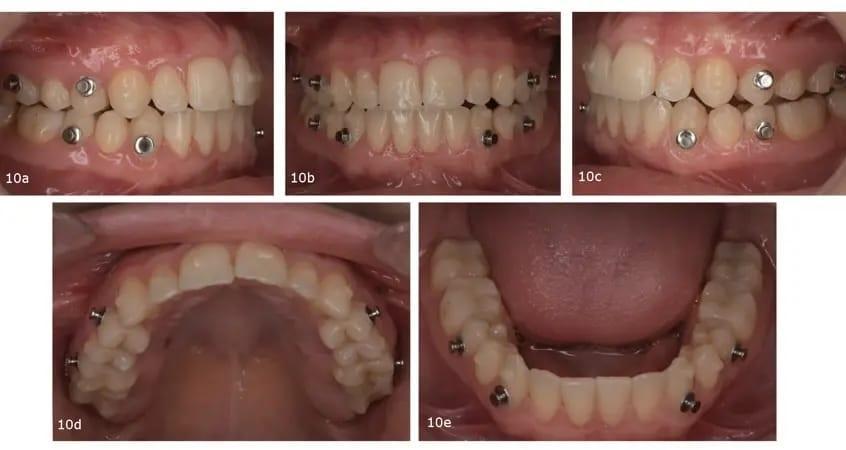

После этапа восстановления, который включал в себя использование 12 пар элайнеров, лечение было продолжено с акцентом на дальнейшее проникновение в заднюю часть верхней челюсти для точной настройки вертикальной коррекции (фото 9). Вторая серия элайнеров была нацелена на окончание лечения с конкретными целями улучшения задней интеркуспации, достижения точной коррекции средней линии и улучшения сагиттальных взаимоотношений с помощью задней IPR и билатеральное использование эластиков III класса (фото 10).

Фото 10a–e: Завершающий этап с элайнерами.